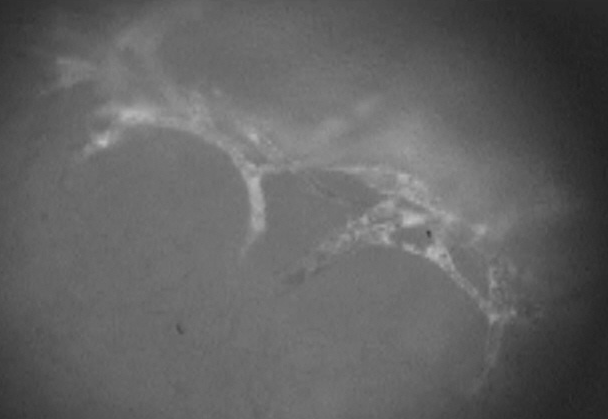

A digital camera was used to take macroscopic pictures, which served as the basis for the subsequent calculations of the wound area. The microcirculation was documented from 24 hours to 11 days after chamber implantation (see Figure 1 [Fig. 1], Figure 2 [Fig. 2], Figure 3 [Fig. 3]). We acquired additional video data by using 400X magnification to film the edges of the wound and used the computer-assisted image analysis program CapImage (Version 7.4, Dr. Zeintl Software; Heidelberg, Germany). Using this program, we also defined parameters such as vessel diameter (µm), midstream red blood cell velocity (RBCV; mm/s), leakage of muscle capillaries and post capillary venules given by the ratio of fluorescence inside vessel vs outside vessel (Ie/Ii). We also determined the functional capillary density (FCD), meaning red blood cell filled capillaries (mm/mm2).

Figure 3: Vessel sprouts visualized using FITC-Dextran as plasma enhancement. Dynamics of vessel development can be analyzed repeatedly over 3 weeks using this model. (bar=10 µm)